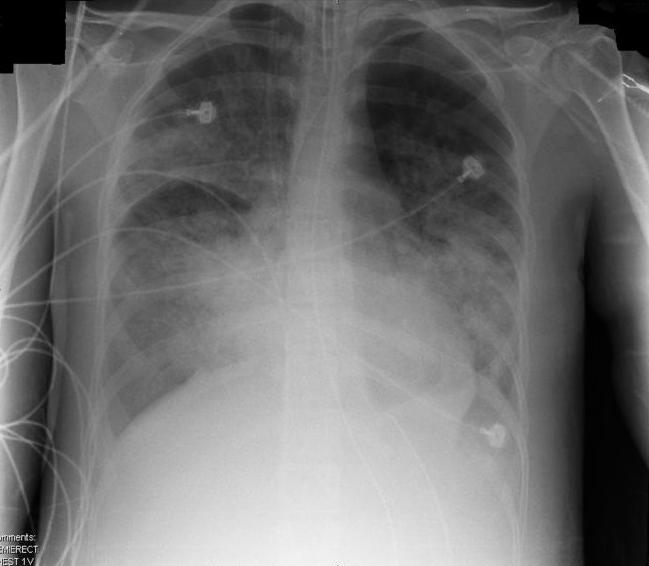

4. Acute respiratory distress syndrome (ARDS)

ARDS occurs when fluid builds up in tiny, elastic air sacs in your lungs. More fluid in your lungs means less oxygen will reach your bloodstream, depriving your organs of the oxygen they need to function.

ARDS typically occurs in people who are already critically ill or who have significant injuries. It will usually develop within a few hours to a few days after the original disease or trauma.

Treatment: There is no cure for ARDS, and the main treatment is supportive care of the patient until the inflammatory process goes away. This could take days or weeks.

The disease is very unpredictable. Many people who develop ARDS don't survive, and the risk of death increases with age and severity. Of those who survive, some recover completely while others experience lasting damage to their lungs and body.